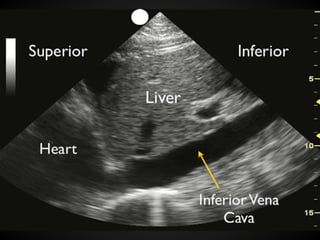

Flat IVC: IVC collapses >50% during the

respiratory cycle

The Significance of the IVC

in Volume Status

The overall size of the vessel is not as

important as the variability.

Increasing the intra-thoracic pressure

would result on an increased IVC size but

might not change the variability. A small

IVC on a hypotensive ventilated patient is

diagnostic of hypovolemia, but a full IVC

does not rule out this diagnosis.

Volume Status Diagnostic ofhypovolemia in hypotensive patients: empty heart or flat IVC In hypovolemia, the ventricular walls will come together or ‘‘kiss,’’ or in cardiologist lingo, an ejection fraction >70% Flat IVC: IVC collapses >50% during the respiratory cycle

The Significance ofthe IVC in Volume Status The overall size of the vessel is not as important as the variability. Increasing the intra-thoracic pressure would result on an increased IVC size but might not change the variability. A small IVC on a hypotensive ventilated patient is diagnostic of hypovolemia, but a full IVC does not rule out this diagnosis.